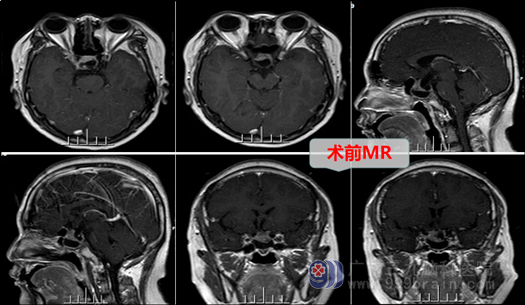

结合患者症状、体征、头颅MR检查,本院头MRI结果示:鞍区病灶--垂体瘤,蓝先生症状明显,有内分泌紊乱,有手术指针。欧阳教授与神经外十科医疗小组分析、讨论后决定:实施手术—“神经内镜下经鼻腔-蝶窦垂体病损切除术” 。术中,在内镜直视下分开鼻中隔粘膜,磨开鞍底骨质,形成鞍底骨窗约1.5cm大小。钩刀“+字型”全层切开硬脑膜。见肿瘤灰白色,质软,正常垂体组织位于左后方,全切肿瘤,鞍膈塌陷,双侧海绵窦内侧壁无肿瘤残留,正常垂体保护良好,无脑脊液漏。术后第二天,患者神志清醒,查体合作,语言清晰,问答切题。